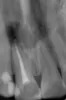

Необходимо удалить кисту 2-х передних зубов. В Крыму пока не нашли клинику, в которой возьмутся за это без удаления зубов. Т.е. сначала удаление, потом чистка с открытием полости через десну, далее полгода на временном протезе и после импланты.

Скажите, возможно ли выполнить все необходимые действия без удаления? Все-таки передние зубы для девушки много значат. Снимки прилагаю.

К сожалению, лечить тут уже нечего. Удаляйте зубы и не тяните, грануляция проникает в носовую перегородку.